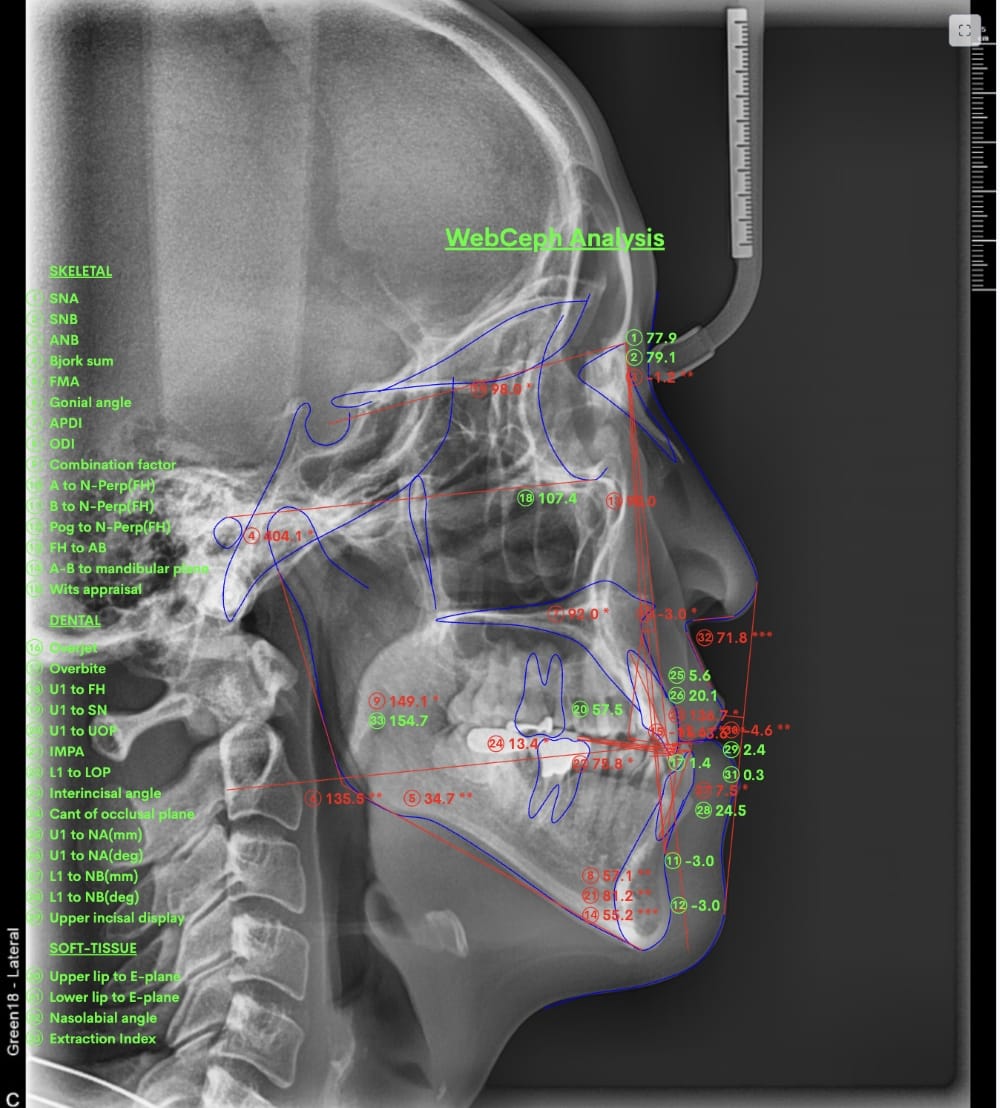

具体的には、口腔内写真やレントゲン写真、特にセファロX線写真を分析し、診断を行います。

例えばセファロX線写真での診断を行い上下の顎の位置のズレが大きいと判断した場合、歯列矯正のみでの治療は困難と判断し、外科的な手術をおすすめする場合もあります。

分析をしますと

- 骨格的な上下あごの前後差は中等度

- 噛み合わせの位置も下あごの奥歯が半分くらい前にズレていた

- 上の前歯が前に傾斜、下の前歯が内側に傾斜しているにもかかわらず、受け口

分析しますと

- 骨格的な上下あごの前後差は中等度〜重度

- 上の前歯が内側に傾斜している

- 骨格的な上下あごの前後差は重度